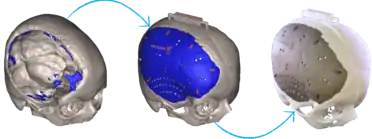

3D-printed implants

3D-printing leverages the power of computer rendering of advanced imaging to tailor implants to each patient, which can then be used to create a physical realization of that implant to use in that individual's surgery.[18][19] 3D-printing of medical devices was first used in the 1990s for dental implants and custom prosthetics but has since been used for various bones and organs such as urinary bladders.[20][21][22]